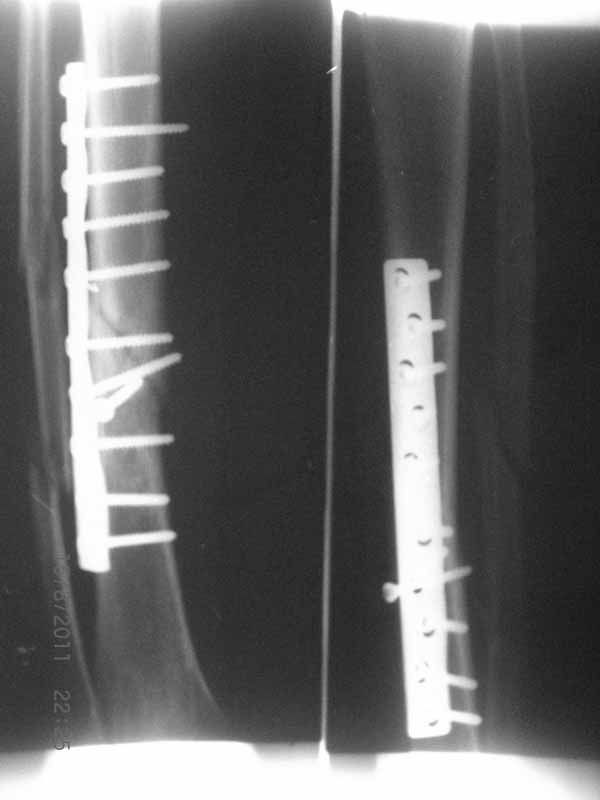

Примерная ситуация. Пациент 37 лет. Синтезировали где-то пластинкой. Попал к нам через 2 месяца.

19 апреля убрали через проколы пластину с винтами, пересекли fibula, наложили аппарат.

Немного потянули по оси, убрали вальгус, ротацию. 22 апреля (на 3-е сутки) заштифтовали окончательно. 29 апреля выписали из отделения. На все ушло 10 дней.

С уважением, Никита Заднепровский